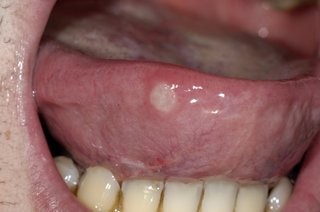

Why you should never ignore a mouth ulcer that won´t heal

Are you prone to getting mouth ulcers? There are a number of different contributing factors and presentations of mouth ulcers; and thankfully most are harmless and heal on their own. However, there are some that can appear very similar but are in fact far more serious. If your mouth ulcer isn’t healing, we recommend you visit us immediately to assess the possibility of mouth cancer. Any mouth ulcer that has been present for more than three weeks must be treated as serious until proven otherwise.

A mouth ulcer, otherwise known as a canker sore or an aphthous ulcer, occurs when there is a break in the skin of the mouth (mucosal lining), exposing the underlying connective tissue. It may have a 'crater-like' appearance and is often red and painful, similar to a blister in the mouth.

Unlike the relatively benign examples mentioned above, oral cancers may initially show up as a mouth ulcer. Oral cancer can present itself in many ways: some people first become aware of an ulcer that won't heal: these lesions are usually a painless mouth ulcer, but it doesn't come and go the way other mouth ulcers do. Any mouth ulcer that has been present for more than three weeks must be treated as serious until proven otherwise. Similarly, if you have developed a red , white or mixed red and white patch, you must urgently seek a professional opinion.